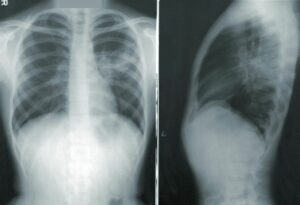

Røntgenundersøgelse